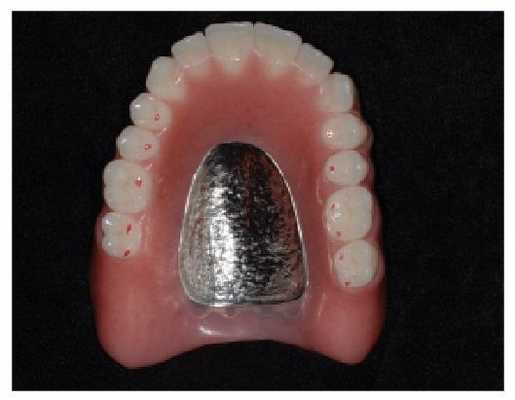

- Протезы на имплантах (при винтовой фиксации протеза, его можно снимать в кабинете стоматолога). Имплант полностью берет на себя функции зуба. Останавливает потерю костной ткани, принимает жевательную нагрузку.

Фиксировать зубные протезы на импланты можно двумя способами:

- На цементе. Современные стоматологические цементы надежно закрепляют реставрации и служат продолжительное время.

- На винтах. Это более сложный вид фиксации, требует большого мастерства от врача. Главным достоинством установки зубных протезов на винты, является возможность снять конструкцию без повреждения, провести необходимые манипуляции, а потом поставить обратно.